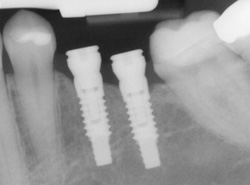

An implant is a synthetic tooth root in the shape of a post that is surgically placed into the jawbone. The “root” is usually made of titanium: the same material used in many replacement hips and knees, and a metal that is well-suited to pairing with human bone. A replacement tooth is then fixed to the post. The tooth can be either permanently attached or removable. Permanent teeth are more stable and feel more like natural teeth.

Implants are versatile. If you are only missing one tooth, one implant plus one replacement tooth will do the trick. If you are missing several teeth in a row, a few strategically placed implants can support a permanent bridge (a set of replacement teeth). Similarly, if you have lost all of your teeth, a full bridge or full denture can be permanently fixed in your mouth with a strategic number of implants.